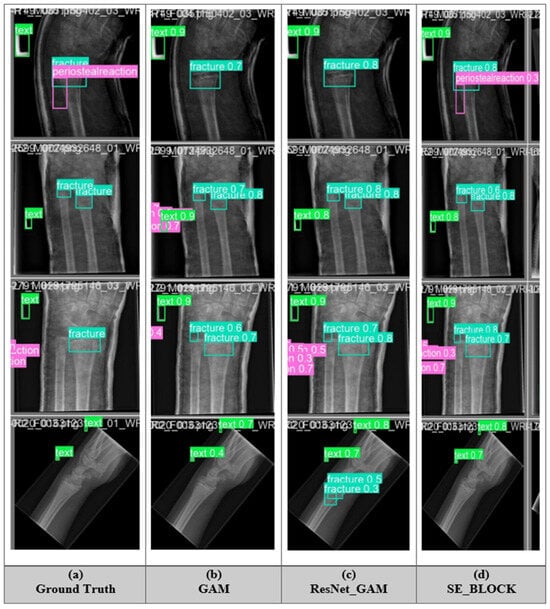

5.5. Fracture Detection of All Model

5.7. Ablation Study